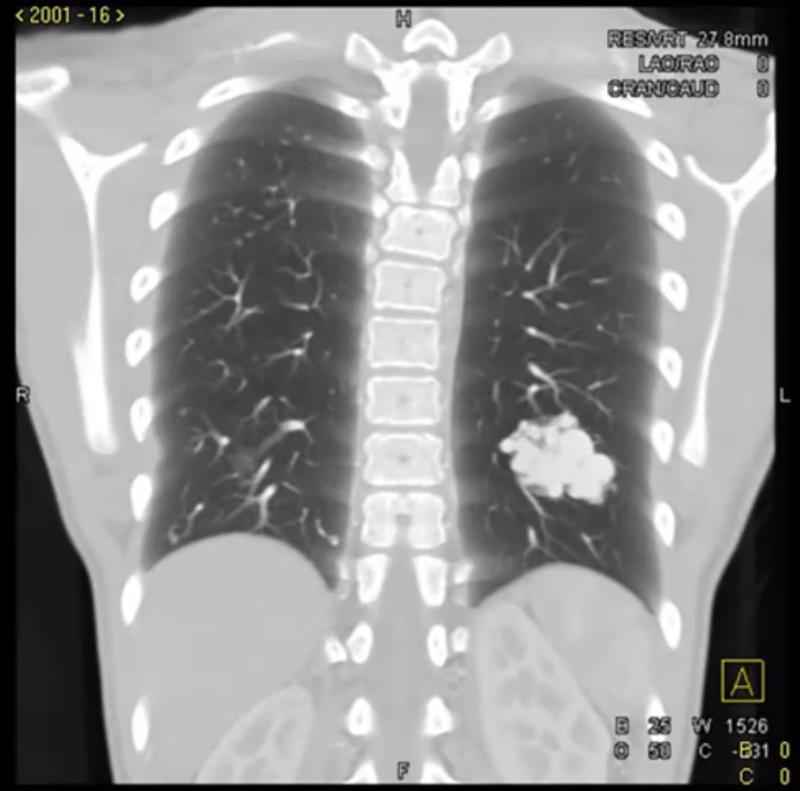

开完检查,我打开影像系统,仔细看了 CT,有五个大小不一的结节,直径在 0.5~2.0cm,其中两个可以看到有动脉并入结节——不过,这和患者的黑便没什么关系。

「肺部 CT 看了一眼,感觉像是多发的动静脉畸形,结合流鼻血和消化道出血,怀疑是遗传性出血性毛细血管扩张症。」主任经典答疑环节开始了,「为了排查可能会危及生命的脑部动静脉畸形,我才让你开了最要紧的头颅磁共振。」

肺部动静脉畸形

图源:YouTube 截图,非本病例